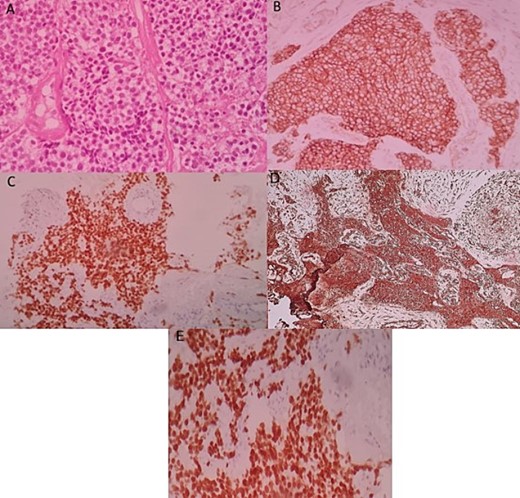

An ultrasound-guided biopsy was performed, and histopathology revealed medium-sized cells arranged in sheets and nests separated by fine fibro-vascular septae. The tumour cells had rounded to oval nuclei, finely granular chromatin, and pale-to-clear scanty cytoplasm (Fig. 3A). Immunohistochemistry showed positivity for: CD99, NKX2-2, FLI1, and vimentin (Fig. 3B–D). WT1, chromogranin, synaptophysin, CD45, CD3, CD20, desmin, and myogenin were negative. Therefore, nephroblastoma, neuroblastoma, lymphoma, and rhabdomyosarcoma were respectively eliminated. ERG was also negative.

Histologic and immunohistochemical staining photomicrographs show sheets of small blue cells, scant cytoplasm with round or oval nuclei (A; H-E stain; original magnification, ×400), membranous expression of CD99 (B; CD99; original magnification, ×200), nuclear expression of NKX2-2 (C; original magnification, ×200), cytoplasmic expression of vimentine (D; original magnification, ×200), and nuclear expression of FLI1 (E; original magnification ×200), findings that are characteristic for EWS.

A molecular study by fluorescent in situ hybridization confirmed the presence of an EWS-FLI1 fusion.